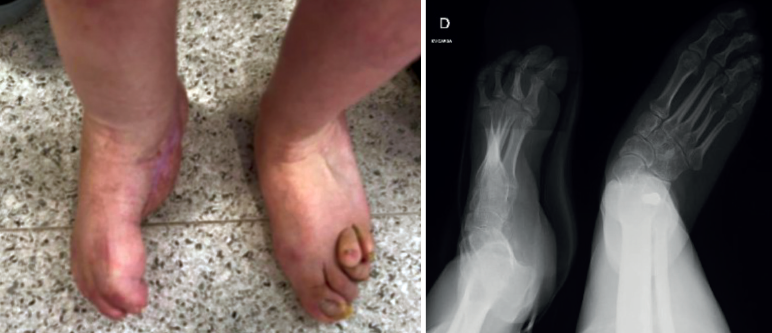

Se trata de una paciente de 34 años en seguimiento en consultas externas por pie zambo derecho congénito. Presenta un tobillo, mediopié y antepié rígidos, un pie equino, varo, aducto y supinado rígido (Figura 1), además de anestesia sensitiva (a consecuencia de lipomeningocele).

Figura 1. Pie zambo derecho con deformidad en equino, varo aducto y supinado.

Sus dedos menores se encuentran en ráfaga media y presenta úlceras periódicas en la base de M5 por hiperapoyo (Figura 2). Además, la paciente nunca había tenido un pie plantígrado.

Tras la retirada del fijador y la inmovilización, se autorizó la carga. La paciente presenta un pie plantígrado e indoloro sin complicaciones asociadas (Figura 4).

Figura 2. Pie derecho con apoyo en M5 y dedos en ráfaga medial. Radiografía en carga.

Figura 4. Pie corregido.